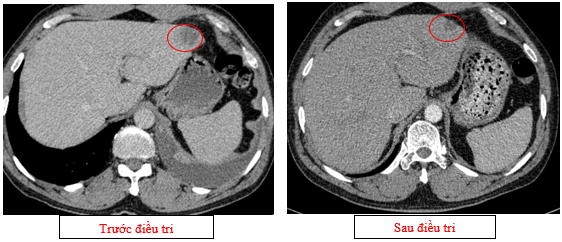

-         Chụp cắt lớp vi tính ổ bụng (11/2025): Nhu mô gan phải có vài nốt, nốt lớn nhất hạ phân thùy VII có nốt giảm tỷ trọng, ngấm thuốc kém sau tiêm đường kính 8mm, hạ phân thùy II, III có nốt giảm tỷ trọng đường kính (tổn thương giảm đáng kể so với phim chụp ngày 08/2025). Các ổ đặc xương rải rác đốt sống ngực thắt lưng, xương cùng và xương chậu hai bên.

Hình 11: Tổn thương ngấm thuốc kém nhu mô gan hạ phân thùy II giảm đáng kể kích thước

Hình 12: Tổn thương ngấm thuốc kém nhu mô gan hạ phân thùy VII giảm đáng kể kích thước

+      Các tổn thương ngấm thuốc kém do di căn tại gan giảm kích thước đáng kể (27mm còn 8mm)